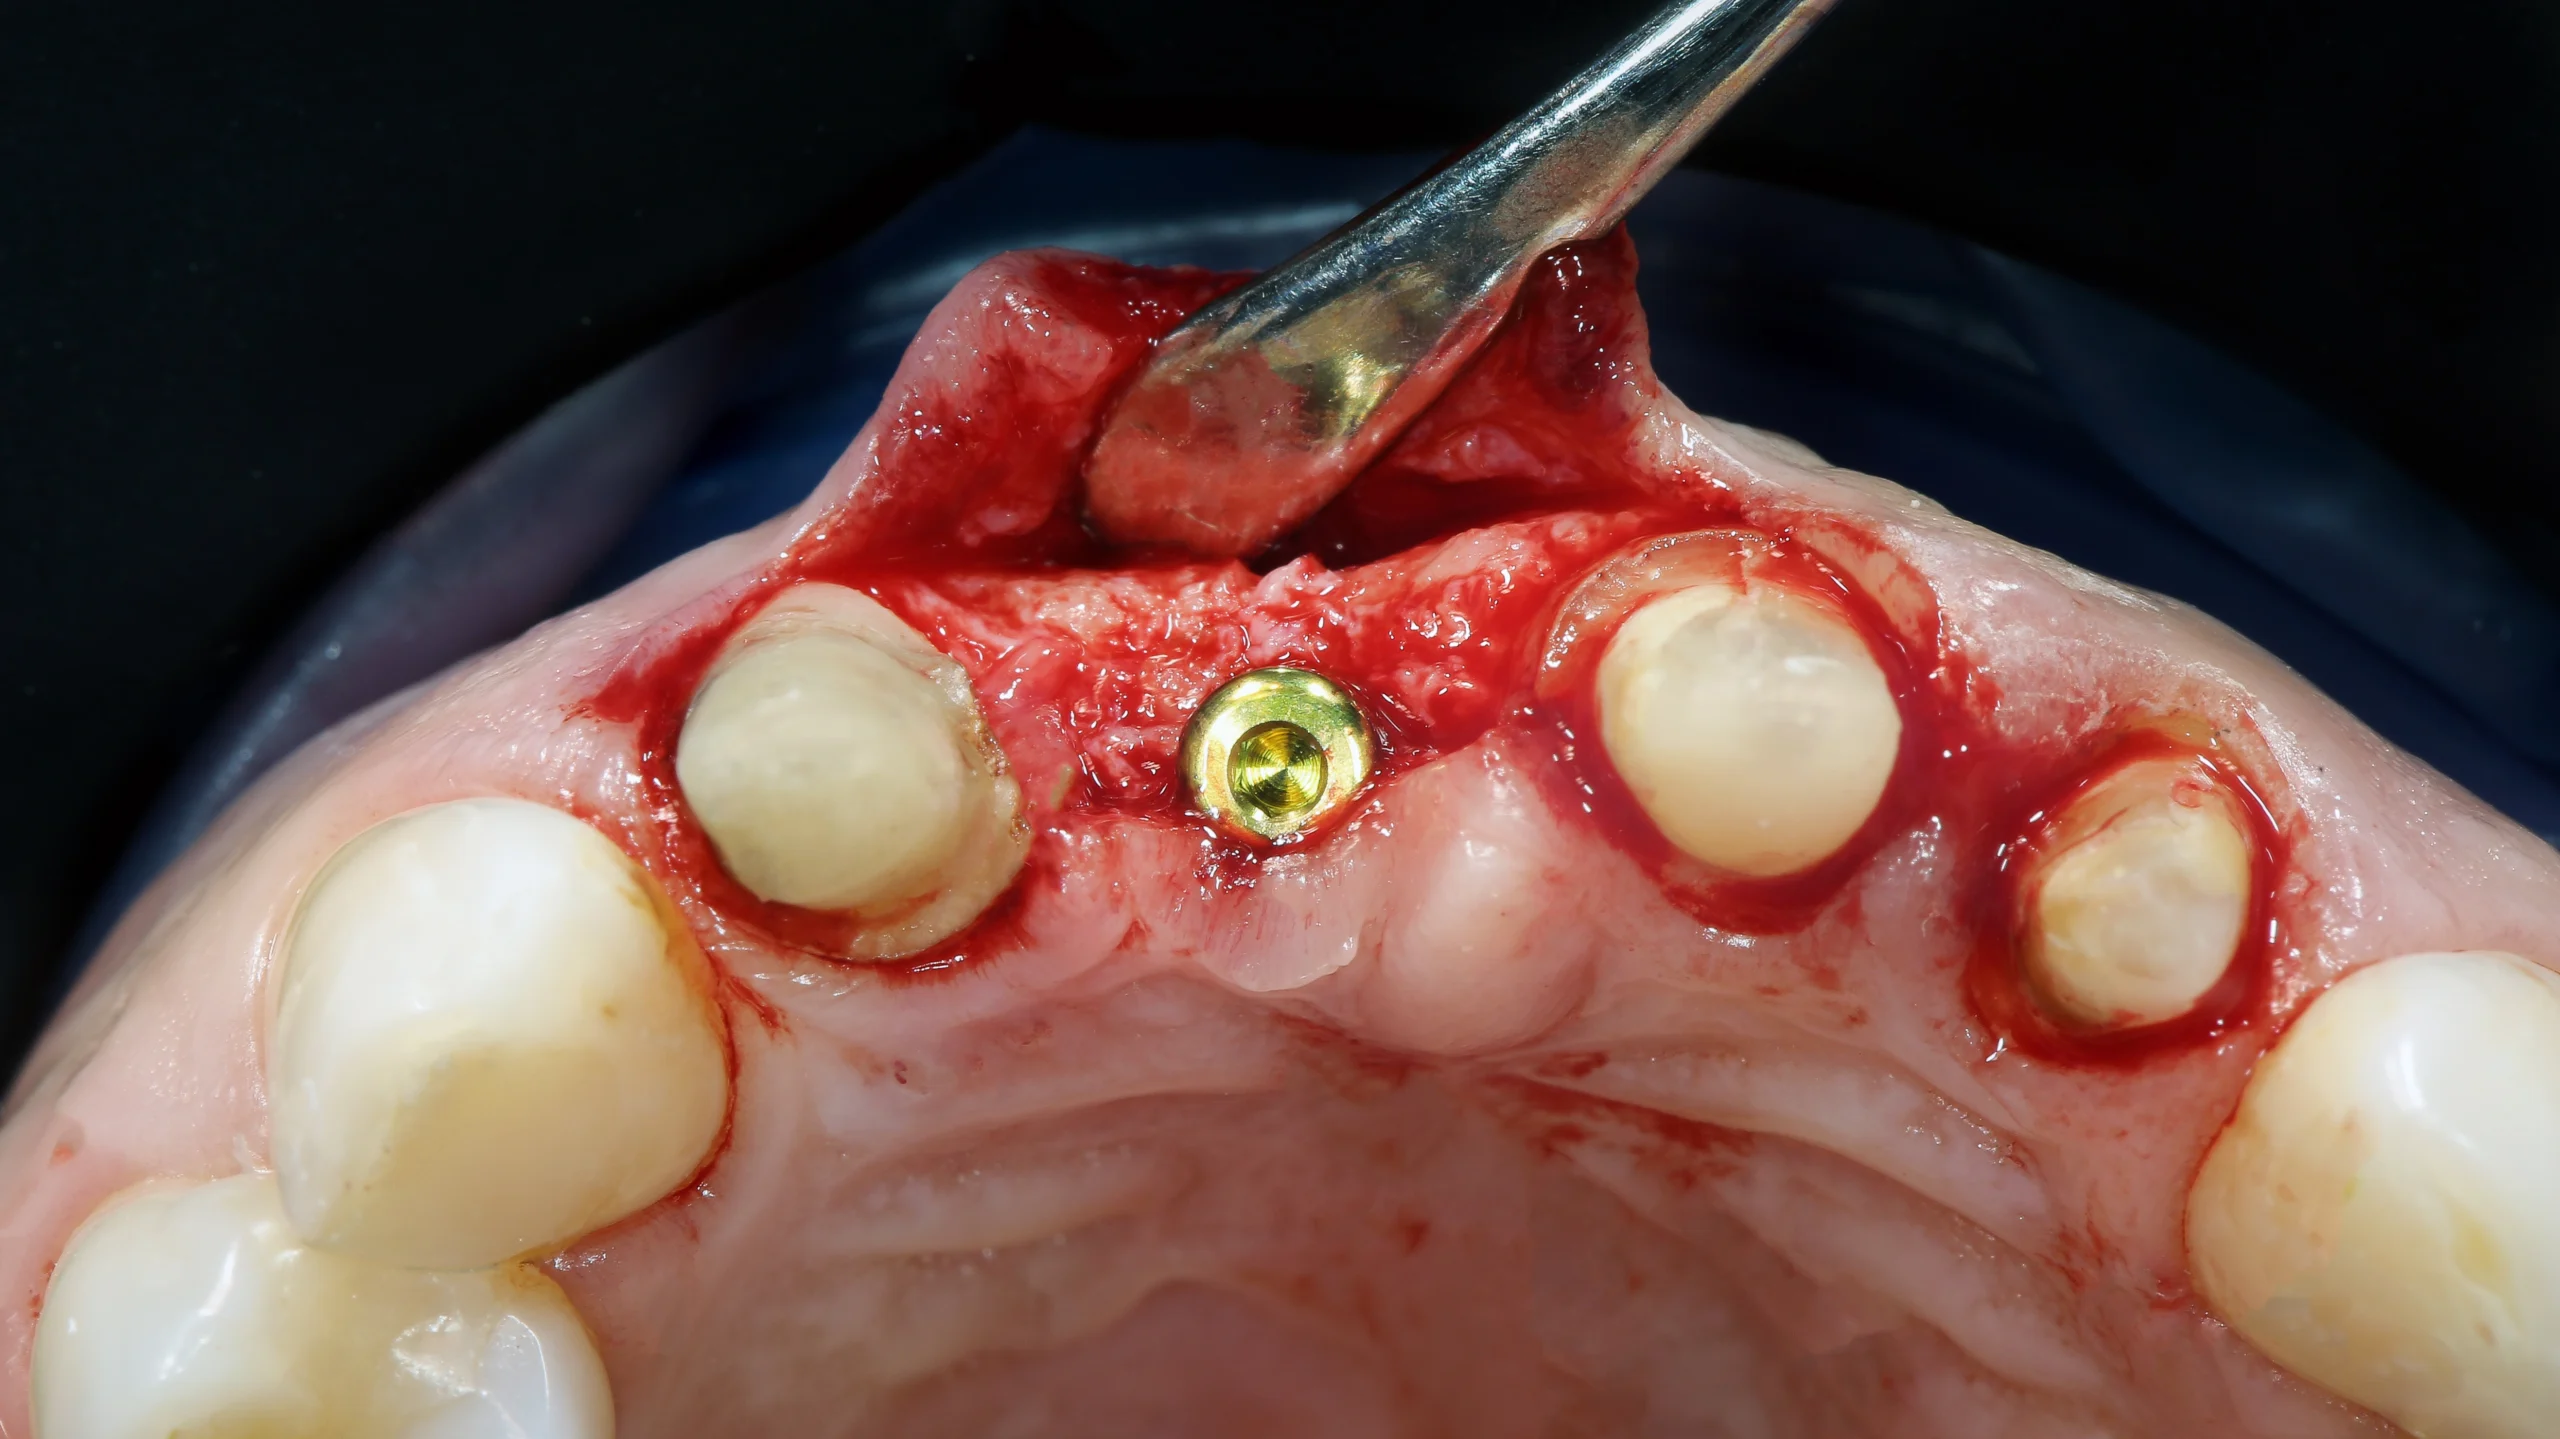

4. جراحی لثه یا برداشت بافت آلوده:

در مواردی که عفونت گسترش یافته باشد، دندانپزشک با جراحی بافت آلوده را خارج میکند تا از آسیب بیشتر به استخوان جلوگیری شود.